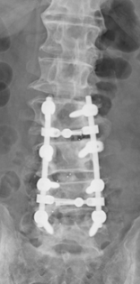

第4腰椎の前方へのすべりのため神経の圧迫を認めています。腰椎後方からずれを金属で整復固定し神経症状が改善しています。

階段状に腰椎が変性すべりをおこしている症例

【術前】

第2, 第3, 第4腰椎に前方への変性すべりを認めます。痛みのため背中を反って立てないことが分かります。MRIではいずれの椎間でも強い脊柱管狭窄が発生し、神経が圧迫されているのが分かります。

【術後】

スクリューとロッド、人工骨を使用した手術により腰椎の階段状変性すべりが整復され、痛みが改善したため腰を反って立つことが出来ています。第2腰椎の前方すべりは軽微であったため、金属は使わず除圧術のみに留めています。